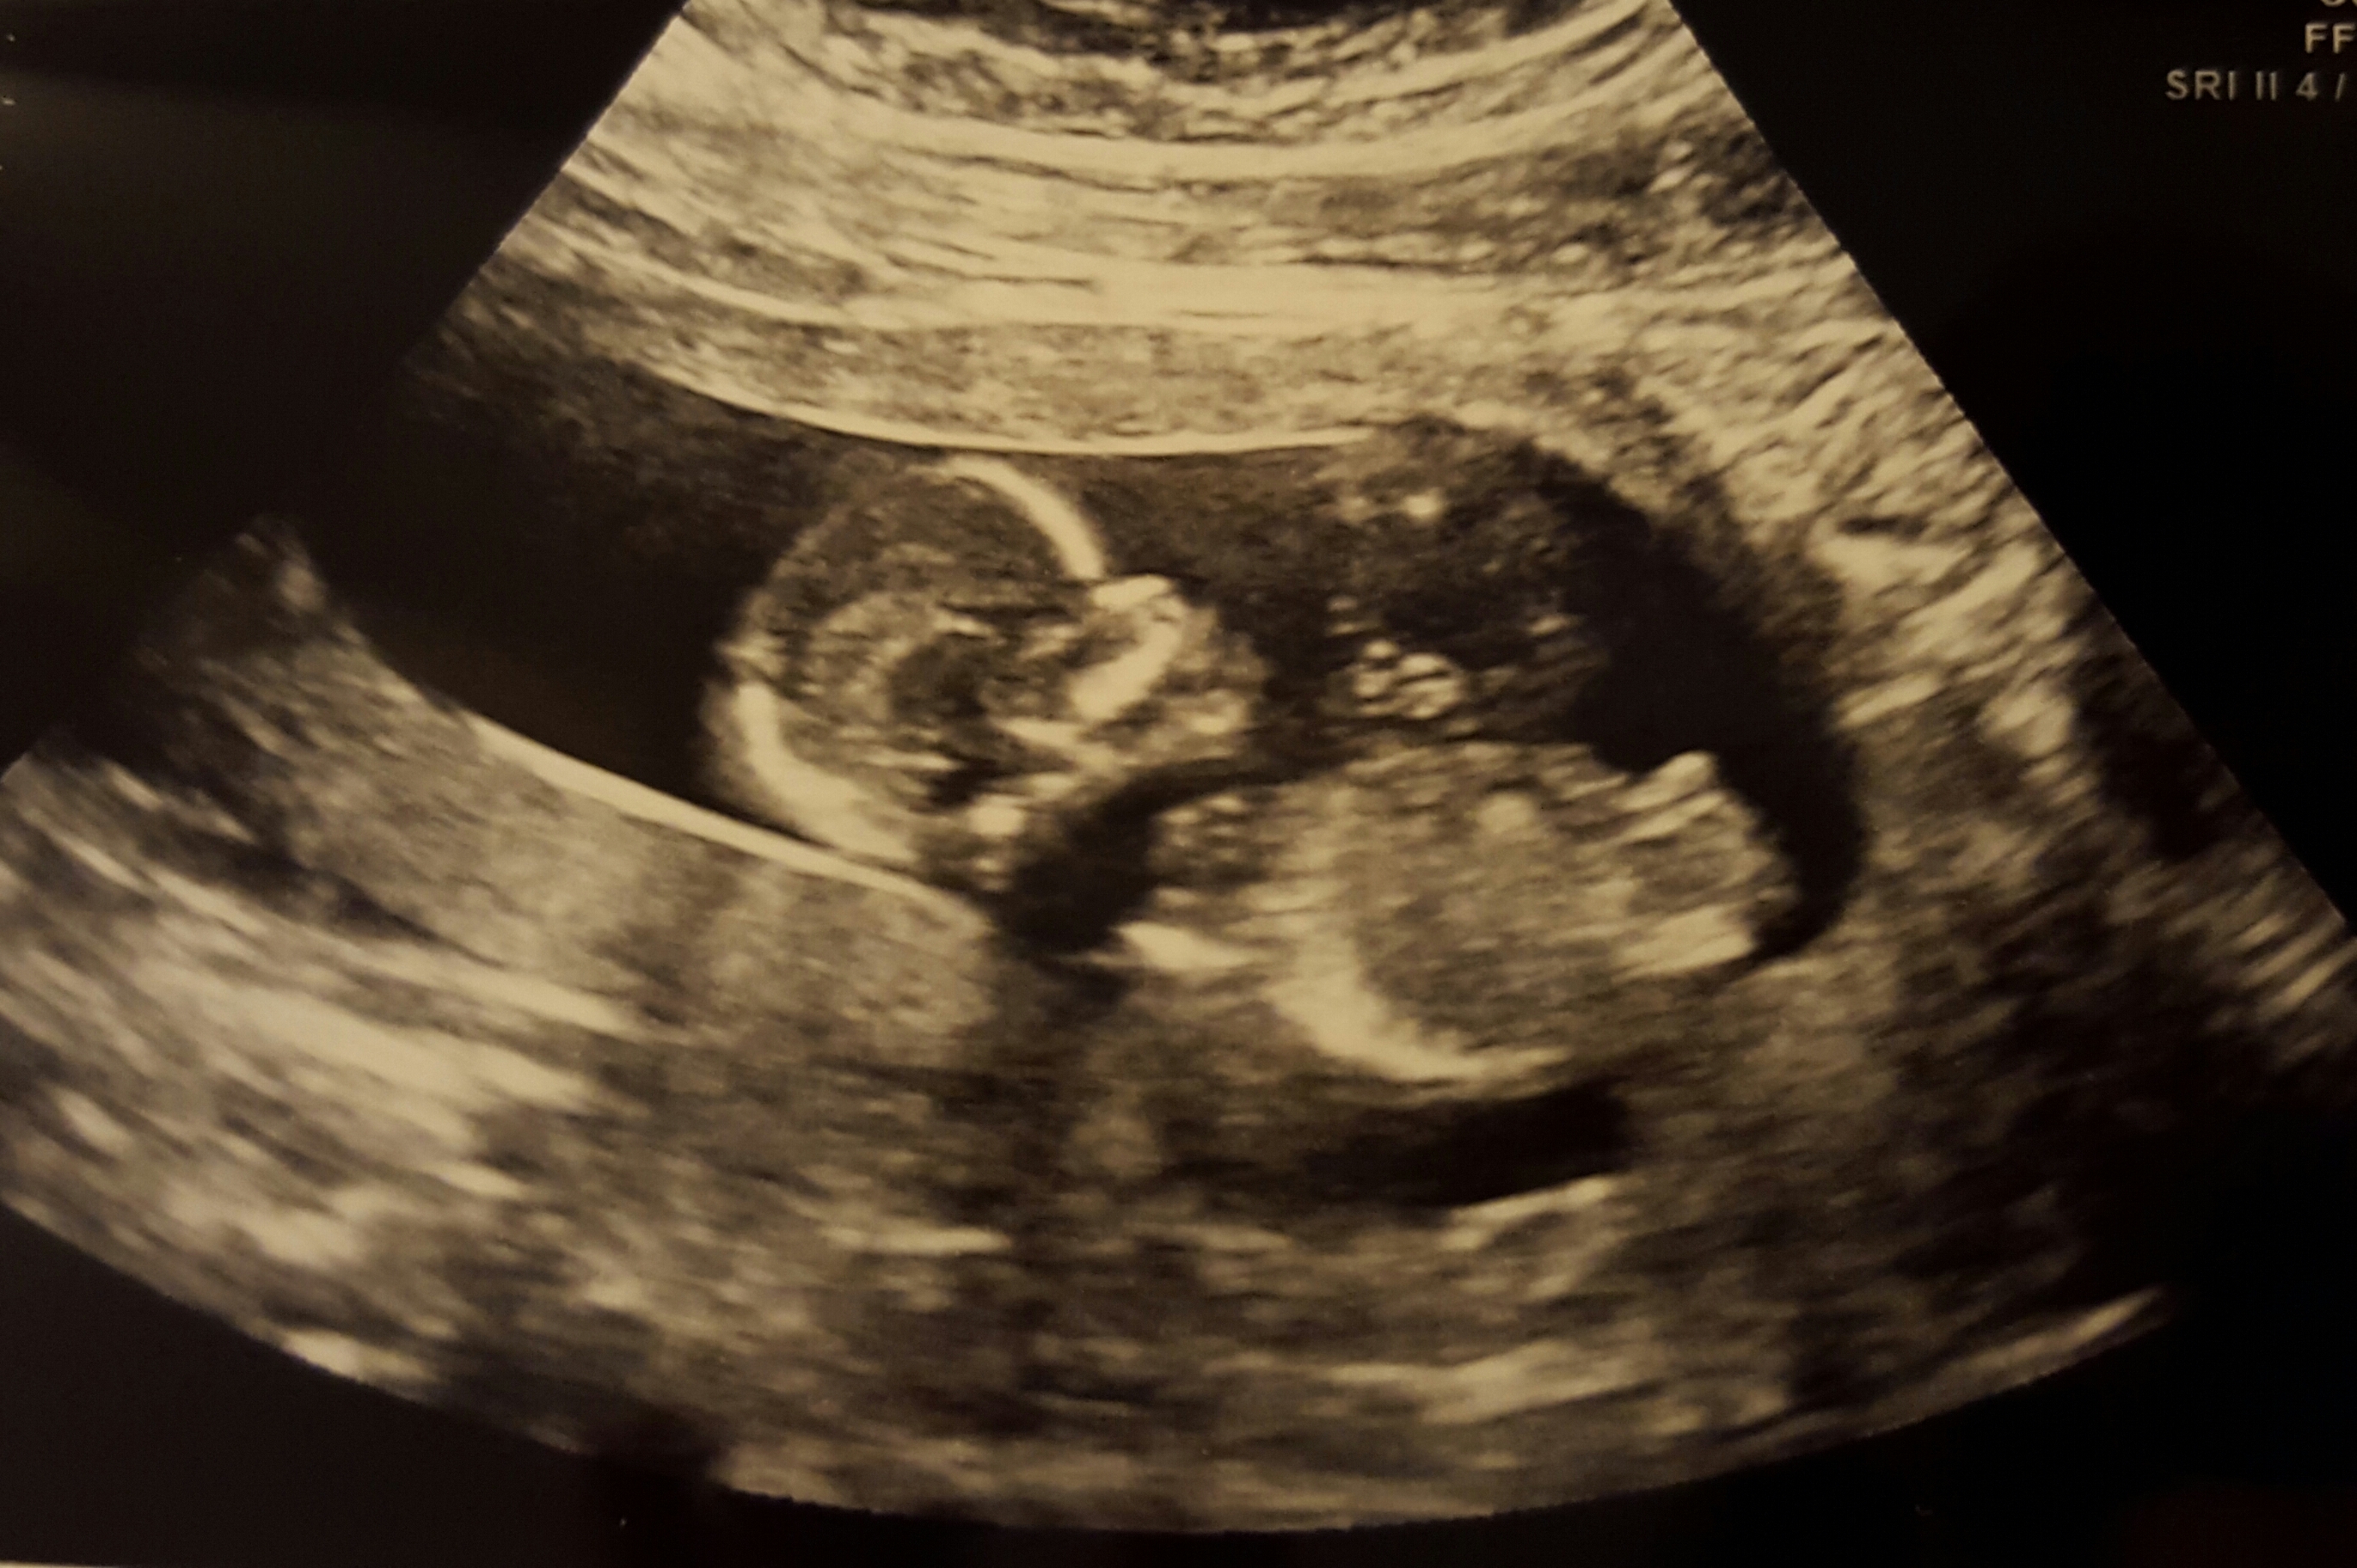

First pic is Baby at 12 weeks, 4 days. Transvaginal ultrasound. ((Sucking their thumb!!! SO CUTE!))

The rest of the pics are at 13 weeks, 4 days. Abdominal ultrasound. In one of the pics it looks like you can see a nub, but the tech said the cord was between the baby's legs (as shown in another pic). Any guesses?! :nails: